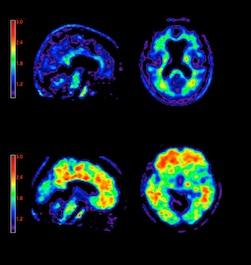

Contrast media, also called contrast agents, are used to enhance the blood and perfusion in tissues. This includes iodine based contrast for on computed tomography (CT), gadolinium based agents for MRI and lipid bubble contrast agents used in ultrasound.